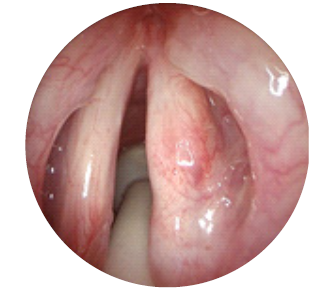

Ao exame objetivo apresentava papilomas na laringe: comissura anterior, terço posterior da corda vocal esquerda e a meio do ventrículo direito. A pontuação total no sistema de estadiamento de Derkay foi de 5 (4+1). O grau de severidade e tipo de disfonia correspondeu a G1R1B0A0S1.

O doente teve alta no dia seguinte a cada procedimento. Foi medicado para o domicílio com esomeprazol 20 mg id antes do pequeno-almoço durante dois meses, antibioterapia com amoxicilina e ácido clavulânico 875 + 125 mg comprimidos 12/12h durante oito dias e analgésicos. Realizou consultas de seguimento na primeira semana e no primeiro mês após o final do ciclo de tratamentos. Na última consulta, no 3º mês após o ciclo de tratamentos, encontrava-se assintomático e ao exame objetivo não foram detetados papilomas. O epitélio das pregas vocais apresentava-se íntegro e normotrófico (fig. 3 e 4).